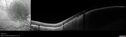

61 year old man with amelanotic choroidal nevus. Vision Normal - Stable over 4 years.

Amelanotic Choroidal Nevus - Multimodal Imaging577 views61 year old man with amelanotic choroidal nevus. Vision Normal - Stable over 4 years.00000